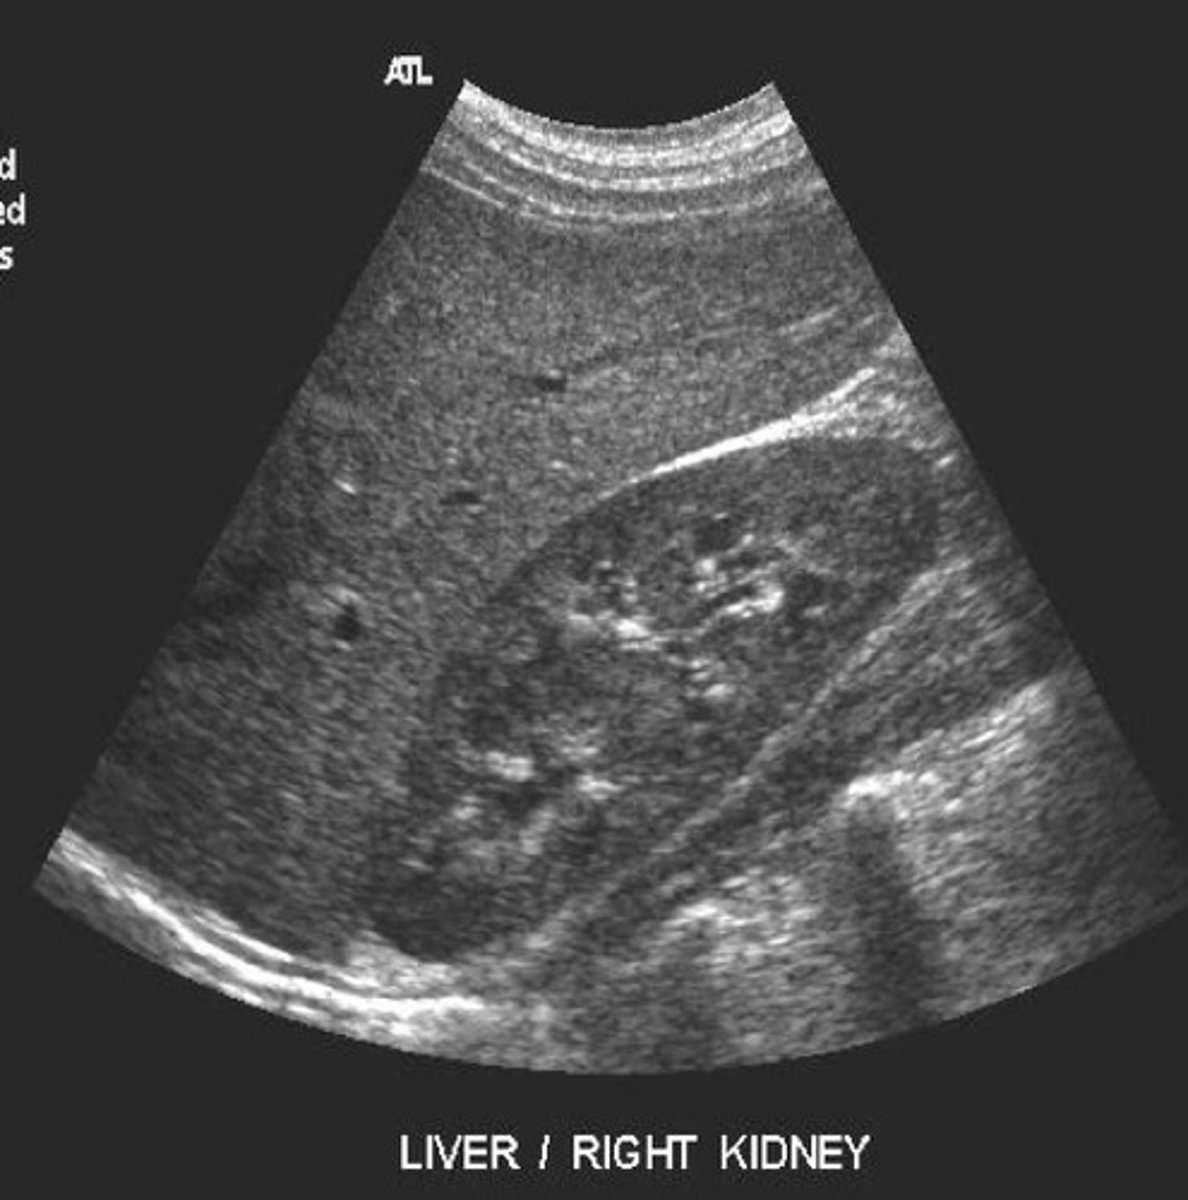

Normal sonographic appearance of liver and kidney

What does this image represent